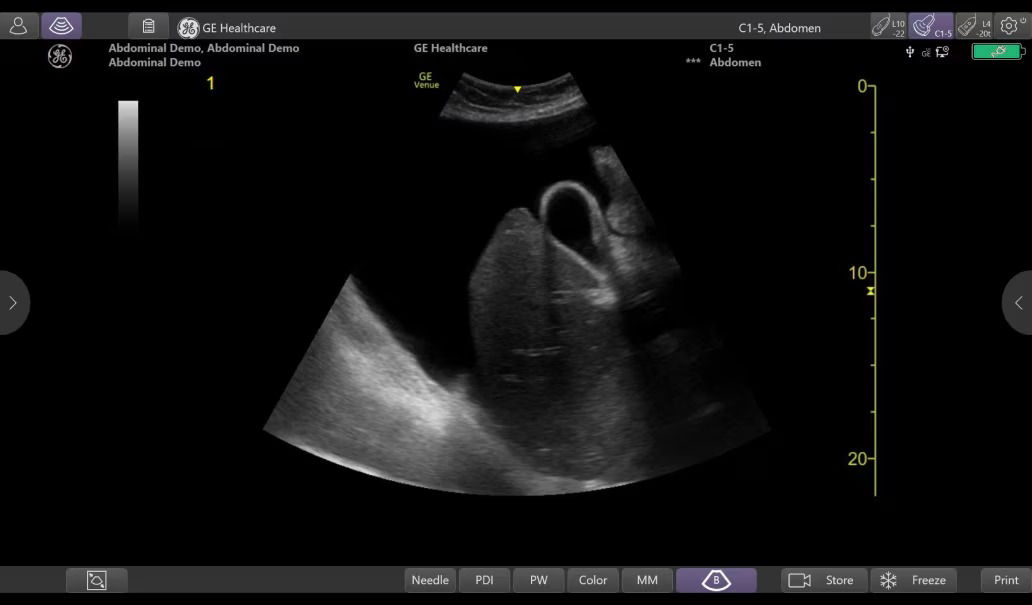

Product tutorial gallery

Get a first-hand look at how Venue supports emergency care practitioners.

venue-point-of-product-tutorial-gallery-desktop-st-en